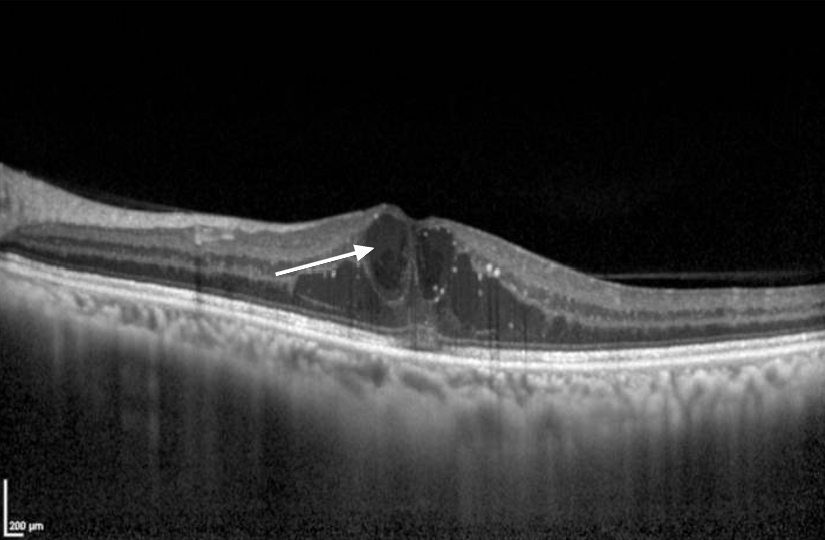

– une acuité visuelle à 5/10 aux deux yeux avec une correction de +1,00 -1 à 90° à droite et +1,75 -1,25 à 85° à gauche ;